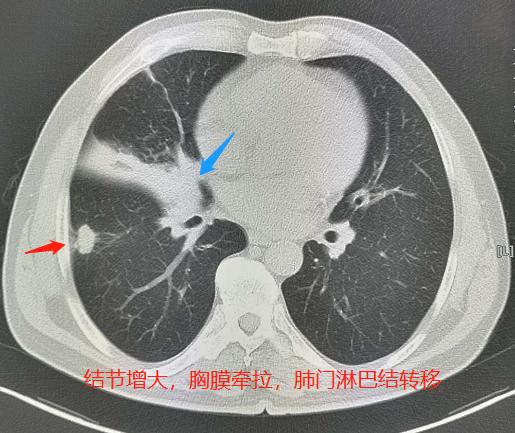

一位60多岁的老妇人,年轻时得过肺结核,每年胸部X光片体检,都是陈旧性肺结核表现:

有一次因为右边肩膀疼来做肺部CT,结果查出肺癌,晚期了:

右上肺这个肿块,围在多发的陈旧性结核灶之间,悄悄长大了!并且发生了纵隔、锁骨上多发淋巴结转移……

如果她早一点选用胸部CT检查,结局会不会不同呢?肯定会!

她一年半后来复查的时候,肿瘤缩小了很多: